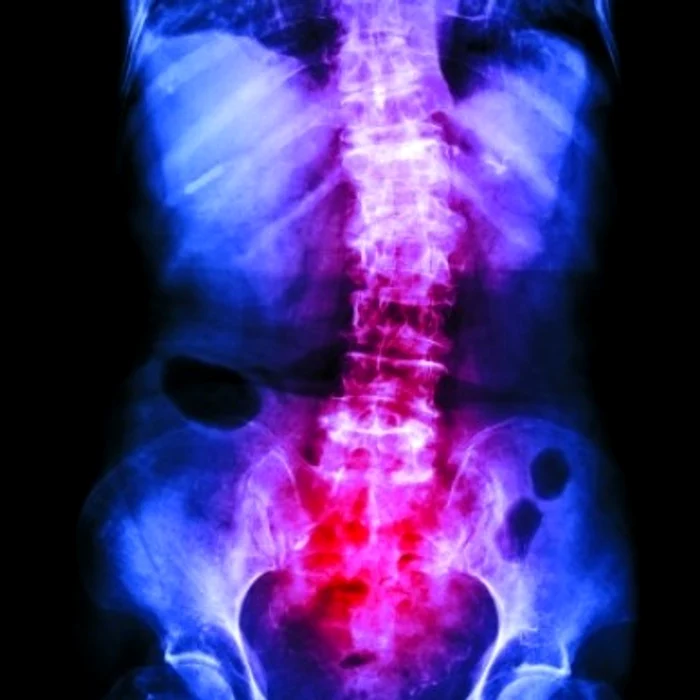

Evoluţia spondilitei anchilozante poate fi oprită sau întârziată, chiar dacă boala nu se vindecă, dacă este diagnosticată devreme şi tratată corect. Cu ajutorul medicaţiei, inflamaţia este stopată, durerea şi senzaţia de înţepeneală sunt combătute. De asemenea, se pot păstra forma şi funcţia coloanei vertebrale. Pe lângă medicamentaţie, exerciţiul fizic este cel mai recomandat, în fiecare zi. Cu cât durerea de spate este lăsată netratată, cu atât pot apărea leziuni ireversibile, care pot avea un impact negativ asupra activităţilor zilnice. „Pacienţii diagnosticaţi cu spondilită anchilozantă sau altă formă de afecţiune de tip inflamator în stadiu precoce pot duce în continuare o viaţă normală dacă urmează tratamentul adecvat prescris de medicul reumatolog şi un program constant de mişcare. Însă, mulţi pacienţi consideră că bolile reumatice sunt boli ale bătrâneţii şi amână consultarea unui medic specialist, deşi simptomele acestora sunt întâlnite într-o măsură importantă şi în rândul populaţiei active, tineri şi chiar copii”, a atras atenţia Conf. Dr. Cătălin Codreanu, Preşedintele Ligii Române contra Reumatismului. Durerile de spate, cele mai frecvente simptome Spondilita anchilozantă implică un proces inflamator la nivelul articulaţiilor şi coloanei, care provoacă durere, înţepenire sau chiar deformarea coloanei vertebrale, cu implicaţii severe la nivel psihosocial şi în viaţa de zi cu zi a pacienţilor.

Durerile de spate pot apărea la orice vârstă, iar unii le descriu drept „zvâcnitoare” şi constată că mişcarea accentuează durerea, iar repausul o ameliorează. Durerile de spate de tip inflamator se instalează progresiv, apar adesea înaintea vârstei de 40 de ani şi nu se ameliorează la repaus. În timpul nopţii, în special în a doua parte, durerea provoacă tulburări de som. Exerciţiile fizice pot reduce durerea şi senzaţia de rigiditate a corpului resimţită în timpul dimineţii. Momentul diagnosticării este esenţial în evoluţia bolii.